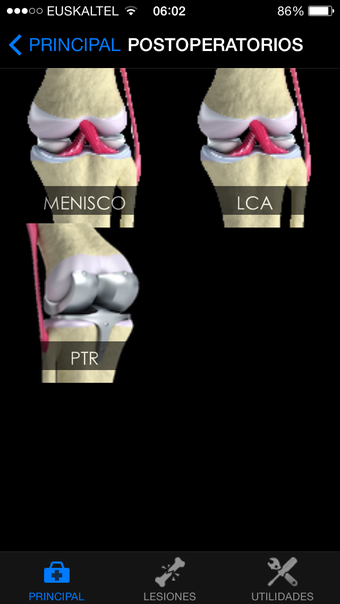

Rodilla App is a free program for Android, that belongs to the category 'Medical'.About Rodilla App for Android

Rodilla App requires Android 9.0 and above. The current version of the program is 7.0.0, and you can run it in English, Spanish and German.